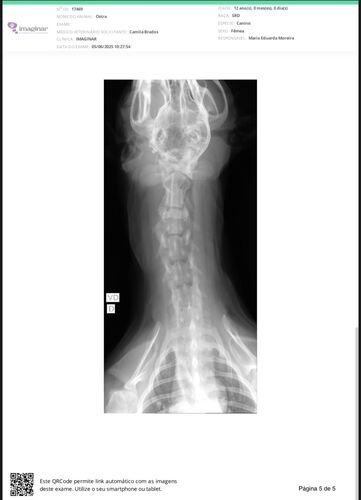

Após algumas consultas veterinárias, fomos informados da possibilidade de a Ostra estar com uma neoplasia tireoidiana, cuja natureza (benigna ou maligna) ainda não foi possível identificar. Para investigar essa condição, entre os meses de junho e julho, já realizamos diversos exames, como ultrassonografia, hemogramas, citopatologia, entre outros, com o objetivo de preparar a realização do exame histopatológico (remoção cirúrgica da massa no pescoço e biópsia).

No entanto, o médico veterinário que acompanha o caso informou que ainda são necessários dois exames fundamentais antes da cirurgia: tomografia computadorizada e ecocardiograma. Esses exames irão verificar quais órgãos podem estar sendo comprometidos pela massa em seu pescoço e se há condições clínicas para submetê-la à anestesia geral.